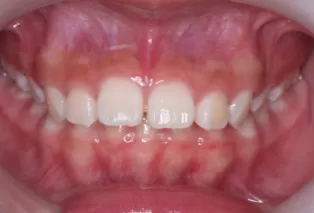

Intraoral photos